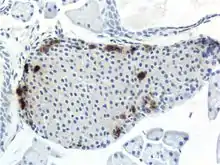

The pancreas serves multiple roles within mammalian organisms. It plays a role in the digestive system and the endocrine system making it an organ and a very important gland.[2] PP cells tend to located in the pancreatic islets, and are one of the rarer pancreatic cell types.[1] Some small clusters may also be found surrounded by exocrine pancreas.[3] They tend to be located in the duodenal part of the pancreas more medially.[3] Given their location in pancreatic islets along with their low population, they are able to respond efficiently to changes in blood sugar, nerve impulses, and chemical signaling through gap junctions or cellular signaling. PP cells show the highest concentration at the head of the pancreas.[1]

PP cells play an important role when it comes to the regulation of plasma glucose as they help to synthesize and release pancreatic polypeptide (PP). As PP cells secrete more pancreatic polypeptide, it has been shown to have a negative effect on insulin secretion giving it anorexic effects on intestinal functionality. These cells have been shown to inhibit functions in the gut and decrease intestinal motor activity as well.[1] In other words, as the secretion of pancreatic polypeptide increases, the secretion of insulin, a peptide hormone, starts to decrease. Pancreatic polypeptide also works to regulate glycogen levels and the amount of secreted substances from gastrointestinal cells and tissue.[4] Within PP cells and its nucleus is the cellular DNA that allows for different proteins to be made that go on to play a role in cellular functions. PP cells are able to produce pancreatic polypeptide through transcription and translation of the PPY gene.[5] Once it is produced, pancreatic polypeptide is shown to be a 36 amino acid long peptide that can be sent out to different areas within the pancreas or organism.[6]

Through different microscopy techniques, the structural related details of PP cells have been able to be better understood. This is inclusive of how big they are, what their cellular membranes look like, the proteins associated with them, and even their size. PP cells are elongated cells. Another one of these details can be noted in insulins secretory granules, or container like buds, that store insulin within a cell. In PP cells, the size of the insulin granules are smaller and spherical and similar to those in alpha cells. This is noted in human PP cells, but different animals have been shown to have different sized granules compared to humans, like rodents. In cats and dogs, PP cells have large granules.[8] In rats, PP cells have few granules, similar to humans. In dogs, some PP cells are located in the walls of the antrum of the stomach.[3]